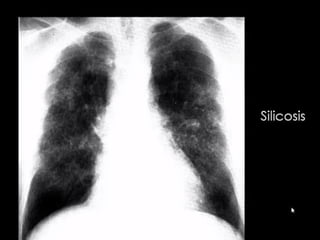

SILICOSIS

Silicosis is a fibrotic pneumoconiosis that is caused by the

inhalation of fine particles of crystalline silicon dioxide

(silica). Occupations such as mining, quarrying, and tunneling are

associated with silicosis.

The classic form is much more common than the acute form and

can be classified as simple or complicated, according to the

radiographic findings:

simple silicosis: pattern of small and round or irregular opacities

complicated silicosis: large conglomerate opacities that equate

to progressive massive fibrosis

PNEUMOCONIOSIS

At CT, features of simple silicosis include:

multiple small nodules that are upper lobe predominant and accompanied by calcifications

hilar and mediastinal lymphadenopathy: may precede the appearance of parenchymal

nodular lesions

calcification of lymph nodes

common and typically occurs at the periphery of the node

this eggshell calcification pattern is highly suggestive of silicosis

Silicosis in a 56-year-old man who worked for 25 years as a

stonecutter. (a) Chest radiograph shows multiple variable-sized nodular

lesions in both lungs, predominantly in the upper and middle

zones. (b) Axial thin-section CT scan (1.0-mm-thick section) obtained at

the level of the azygos arch shows multiple small nodules with a

perilymphatic (centrilobular plus subpleural) distribution in the upper

lobe of both lungs. Note the tendency toward coalescence of the nodules

in the lung periphery (arrows).

Radiography of silicosis and CWP are similar:

Simple: micronodules < 1 cm, upper lungs, hilar/mediastinal lymphadenopathy, egg shell

calcifications

Complicated known as progessive massive fibrosis (PMF): aggregation of nodules into

large masses, may cavitate

Increased risk for TB